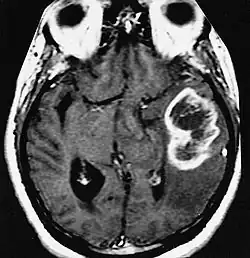

An example of a ring-enhancement around a lesion in gliobastoma. In tumefactive multiple sclerosis, the ring-enhancement is open, not forming a complete ring.

Diagnosis of tumefactive MS is commonly carried out using magnetic resonance imaging (MRI) and proton MR spectroscopy (H-MRS). Diagnosis is difficult as tumefactive MS may mimic the clinical and MRI characteristics of a glioma or a cerebral abscess. However, as compared to tumors and abscesses, tumefactive lesions have an open-ring enhancement as opposed to a complete ring enhancement.[1] Even with this information, multiple imaging technologies have to be used together with biochemical tests for accurate diagnosis of tumefactive MS.[36]

MRI diagnosis is based on lesions that are disseminated in time and space, meaning that there are multiple episodes and consisting of more than one area.[39] There are two kinds of MRI used in the diagnosis of tumefactive MS, T1-weighted imaging and T2-weighted imaging. Using T1-weighted imaging, the lesions are displayed with low signal intensity, meaning that the lesions appear darker than the rest of the brain. Using T2-weighted imaging, the lesions appear with high signal intensity, meaning that the lesions appear white and brighter than the rest of the brain. When T1-weighted imaging is contrast-enhanced through the addition of gadolinium, the open ring enhancement can be viewed as a white ring around the lesion.[40] A more specific MRI, Fluid attenuation inversion recovery (FLAIR) MRI show the signal intensity of the brain. Subjects with tumefactive multiple sclerosis may see a reduction of diffusion of the white matter in the affected area of the brain.[11]